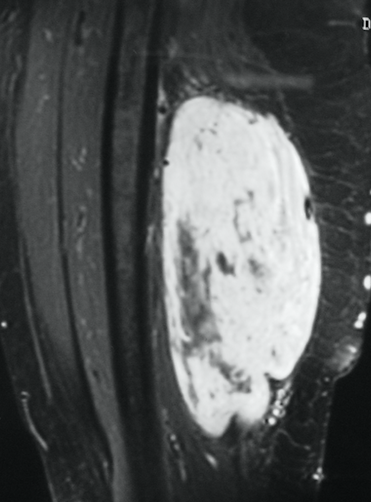

Radiographic imaging is used to help form a diagnosis. These include X-Ray, MRI, CT and Bone Scans

An example of an MRI is shown.